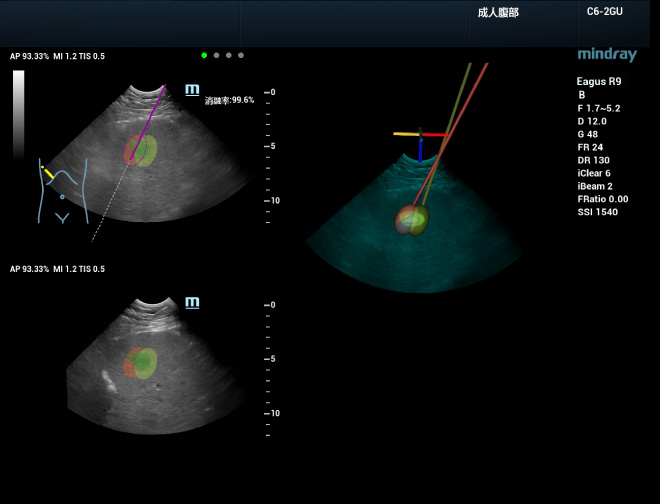

Davantage de confiance pour rÃĐaliser le traitement

Lors de la planification de l'ablation en 3D, l'ablation peut Être simulÃĐe afin de mettre au point une stratÃĐgie de traitement efficace pour les lÃĐsions de grande taille qui doivent Être retirÃĐes à l'aide de plusieurs aiguilles. L'ÃĐtendue d'ablation pour les aiguilles individuelles est dÃĐfinie dans un premier temps, puis les aiguilles pour l'ablation sont positionnÃĐes dans la simulation. Un plan optimal peut Être finalisÃĐ en observant l'affichage en temps rÃĐel du taux de couverture de la lÃĐsion. Ce procÃĐdÃĐ prend en charge l'affichage multi-angles tridimensionnel, pour une observation intuitive et multidimensionnelle de la couverture d'ablation dans l'ensemble de la tumeur. L'aiguille peut ensuite Être guidÃĐe dans la tumeur rÃĐelle selon le trajet planifiÃĐ, et la couverture d'ablation est mise à jour en temps rÃĐel selon l'insertion rÃĐelle de l'aiguille. Gr?ce à uHit Fusion, l'ensemble du processus d'ablation peut Être mieux planifiÃĐ et standardisÃĐ, ce qui rÃĐduit ainsi la dÃĐpendance vis-à -vis de l'expÃĐrience de l'opÃĐrateur.